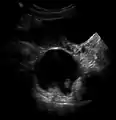

A small (4 cm) dermoid cyst of an ovary, discovered during a C-section

While all ovarian cysts can range in size from very small to quite large, dermoid cysts are not classified as functional cysts. Dermoid cysts originate from pluripotent germ cells (which are present at birth) that differentiate abnormally, developing characteristics of mature dermal cells. Complications exist, such as torsion (twisting), rupture, and infection, although their incidence is rare. Dermoid ovarian cysts which are larger present complications which might require removal by either laparoscopy or laparotomy (traditional surgery).[3][4] Rarely, a dermoid cyst can develop in the vagina.[5][6][7]